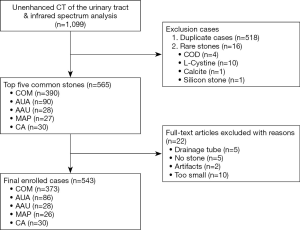

A total of 543 patients were finally collected, and the five most common stones were: COM, anhydrous uric acid (AUA), carbonate apatite (CA), ammonium urate (AAU), and magnesium ammonium phosphate (MAP). Among them, there were 373 cases of COM calculi and 170 of non-COM calculi. The case screening process is shown in Figure 1.

Of the 543 patients, 373 were in the COM group and 170 in the non-COM group (including 86 AUA, 28 AAU, 26 MAP, and 30 CA stones). There were 186 cases of pure calculi (142 COM, 38 AUA, and 6 AAU), and 357 cases were mixed calculi; among which, MAP and CA were all mixed. In the COM group, there were 275 men and 98 women; age 45.55±16.14 years, including 23 aged <18 years and 350 >18 years; 7 cases of recurrence after 1 year and 3 after 2 years; 1 case of combined horseshoe kidney malformation; 160 cases of single and 213 cases of multiple stones; 161 cases on the left, 127 cases on the right, and 73 bilateral cases. There were 177 cases of kidney stones, 92 ureteral stones, 12 bladder stones, 88 kidney–ureteral stones, 4 kidney–bladder stones, 24 staghorn stones, and 349 nonstaghorn stones (Table 1).